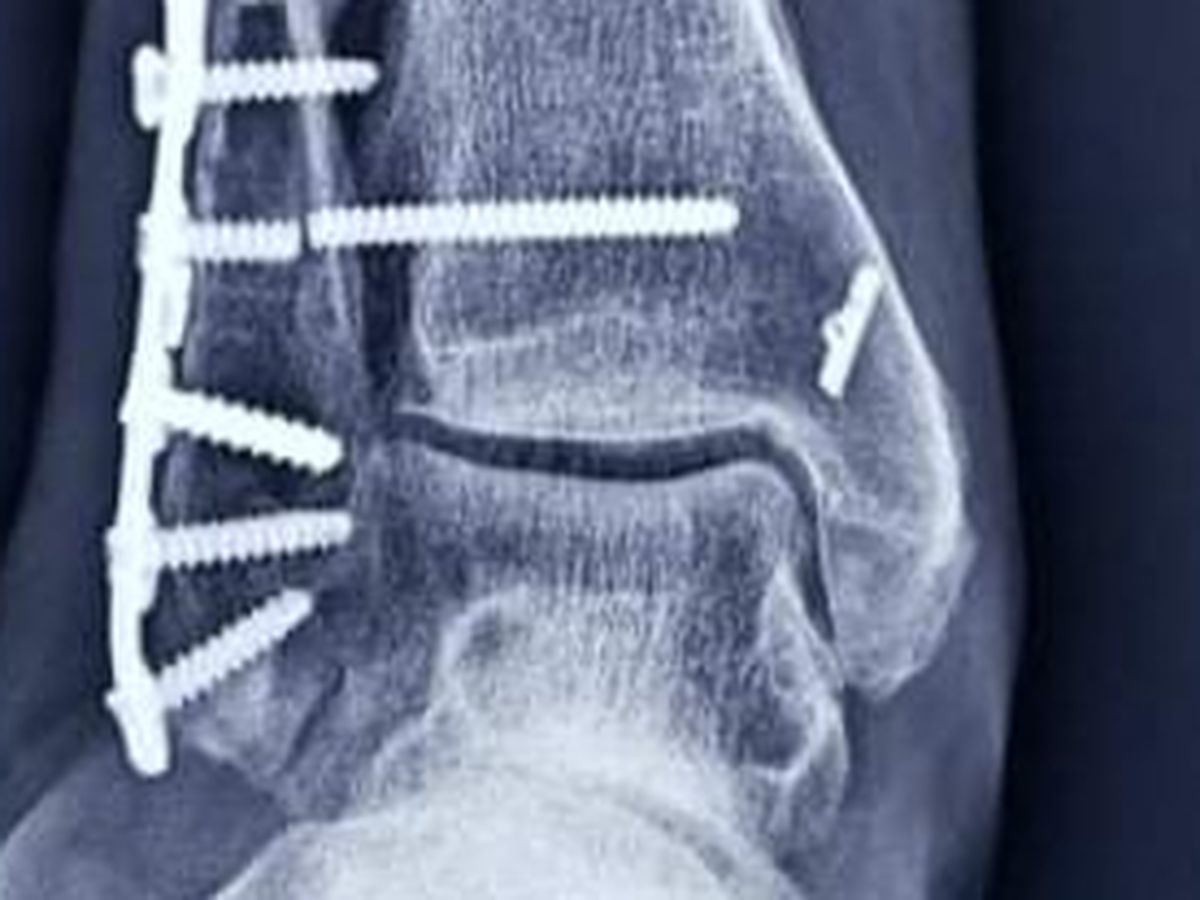

Brandi broke her leg in 3 spots (trimalleolar fracture) in Oct 2020 outside of the states and the dr opted to not do surgery.. after 12 weeks in a cast, she was released with no further care.. she sought the guidance of 2 different physical therapists. It was the 2nd PT who told her to seek a 2nd opinion with another ortho. The Dr. said it was too late to do the surgery she needed since her bones were starting to fuse. She started looking for someone in States. She found a surgeon that would see her via zoom and he agreed she needed to fix her ankle asap.. After making everything happening to get the first surgery (she got a loan because insurance would only cover 40%) they did a total ankle reconstruction and found she had a dislocated ankle bone as well. She healed great and started walking mid August. In the end of Sept, the screw going through both bones broke which is causing her a lot of pain. She saw her surgeon in end if January who told her she has scarring behind the plate and arthritis in her ankle.. He needs to remove her hardware and scrape out her ankle if he can. It is her only hope at less pain.